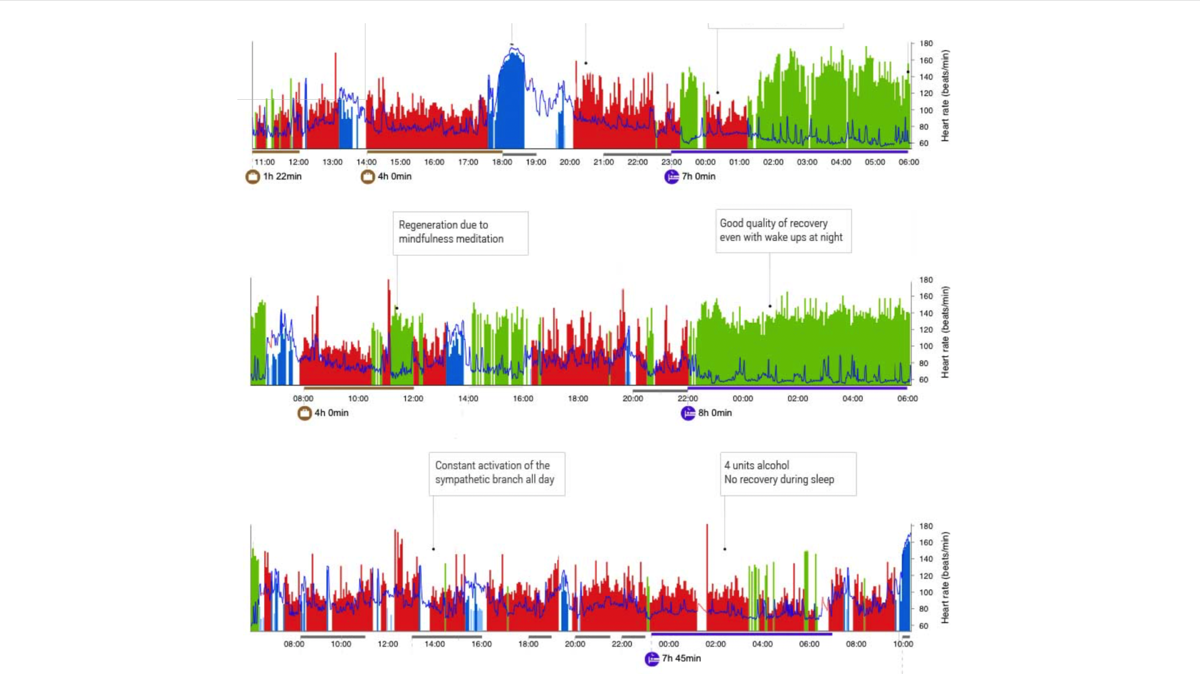

顎関節症からのストレスがどの程度に人に影響を与えているかは、生体情報として心拍を記録したり、神経伝達物質を測定することで確認できる。

ストレスをグラフ化すると1日のストレス状況が理解しやすい。顎関節症では終日ストレス状態にあり、全く休まらないような重症例も経験した。常にストレス状態が継続すれば、他の疾患発症のリスクも高まる(海外研究機関送付)。